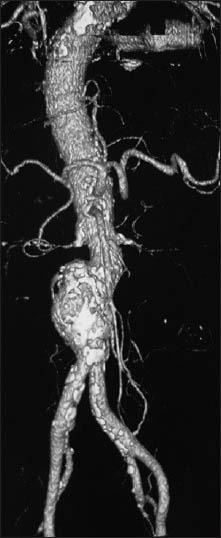

Diagnosis of chronic inflammatory syndrome is often a challenge. In dialysis patients, this condition leads to resistance to recombinant human erythropoietin (rHuEPO). We here report a case of a 72-year-old male undergoing chronic hemodialysis and developed rHuEPO resistance without any obvious etiology. Investigations showed a partially thromosed aneurysm of the infrarenal aorta. Antiplatelet therapy was started with a satisfactory outcome.

慢性炎症综合征的诊断常常具有挑战性。在透析患者中,这种情况会导致对重组人促红细胞生成素(rHuEPO)产生抵抗。我们在此报告一例72岁男性慢性血液透析患者,该患者出现了rHuEPO抵抗且无任何明显病因。检查显示肾下腹主动脉有部分血栓形成的动脉瘤。开始抗血小板治疗,结果令人满意。